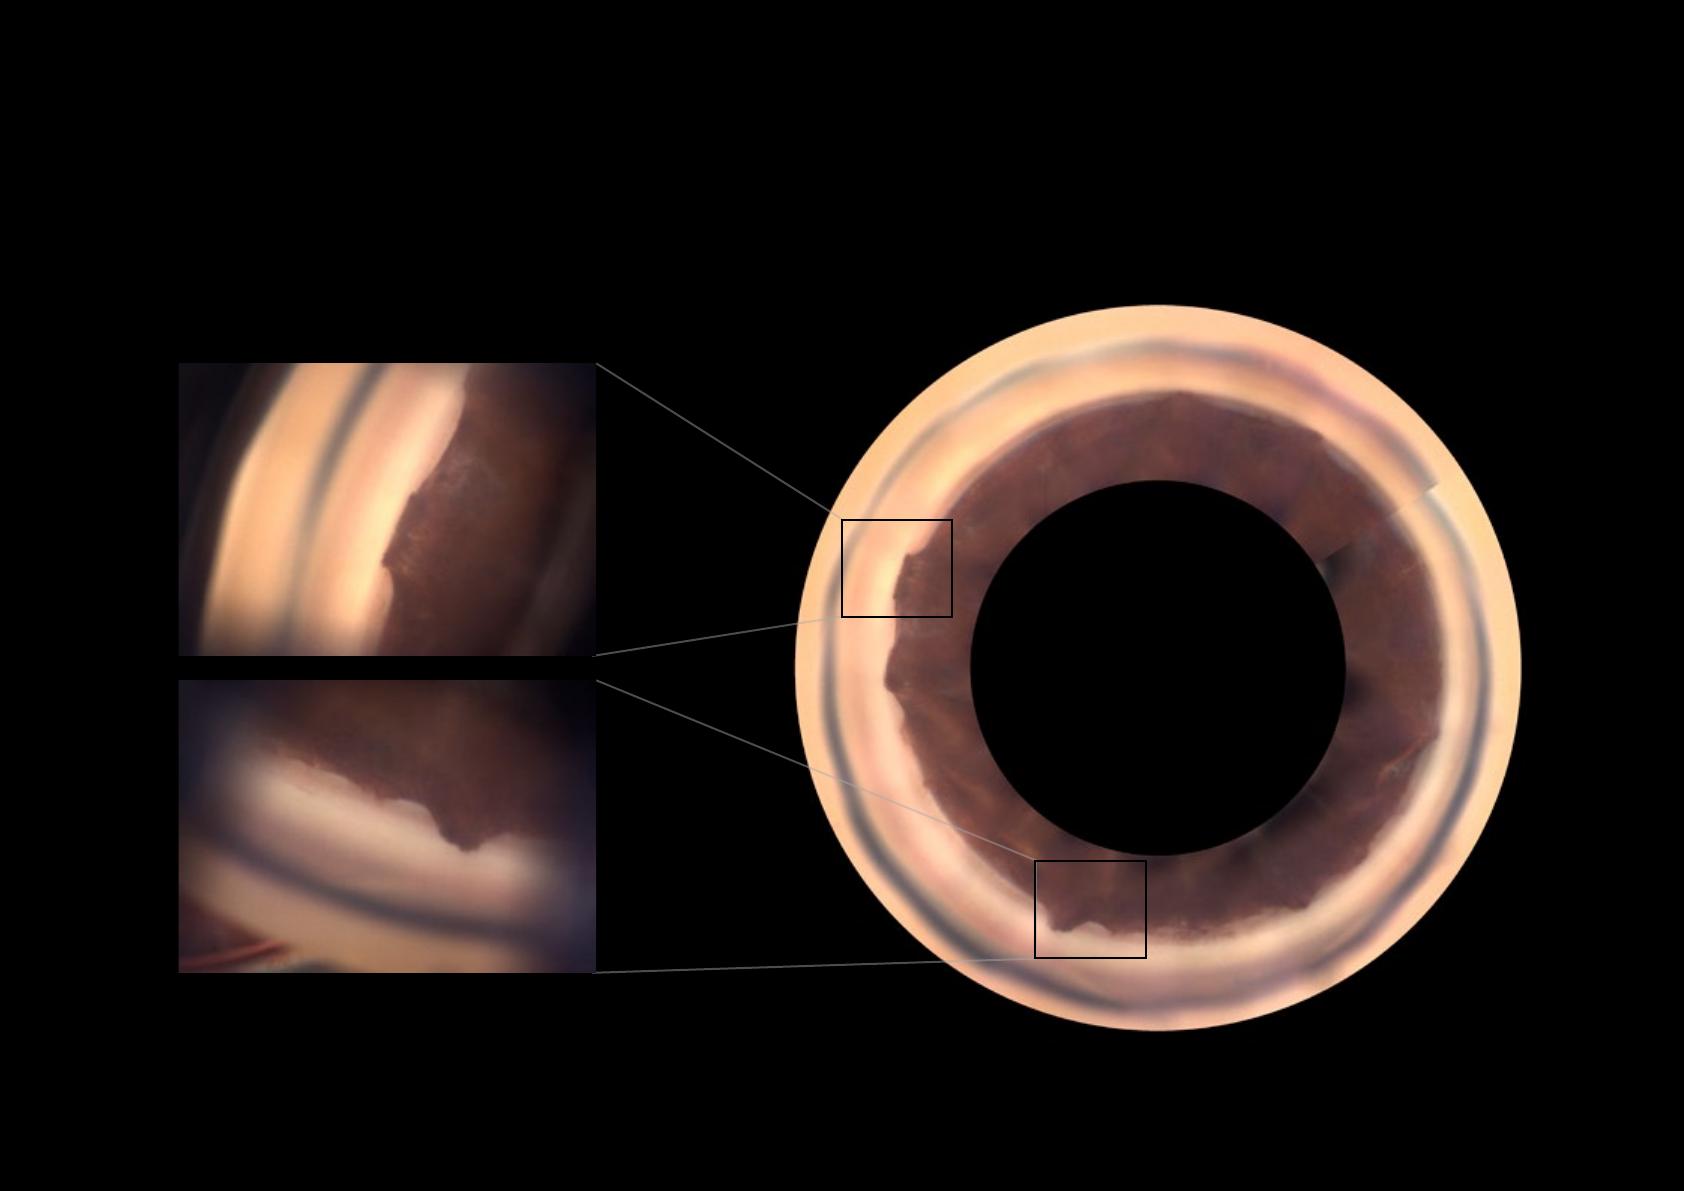

Glaucome chronique par fermeture de l’angle

Avec l’aimable autorisation du Professeur Jean-Paul Renard, Paris

Zones d’adhérence de l’iris au niveau du trabéculum. Elles sont

à l’origine d’une fermeture progressive de l’angle. Elles risquent de

perturber la fonctionnalité de l’angle irido-cornéen.

SYNÉCHIES ANTÉRIEURES